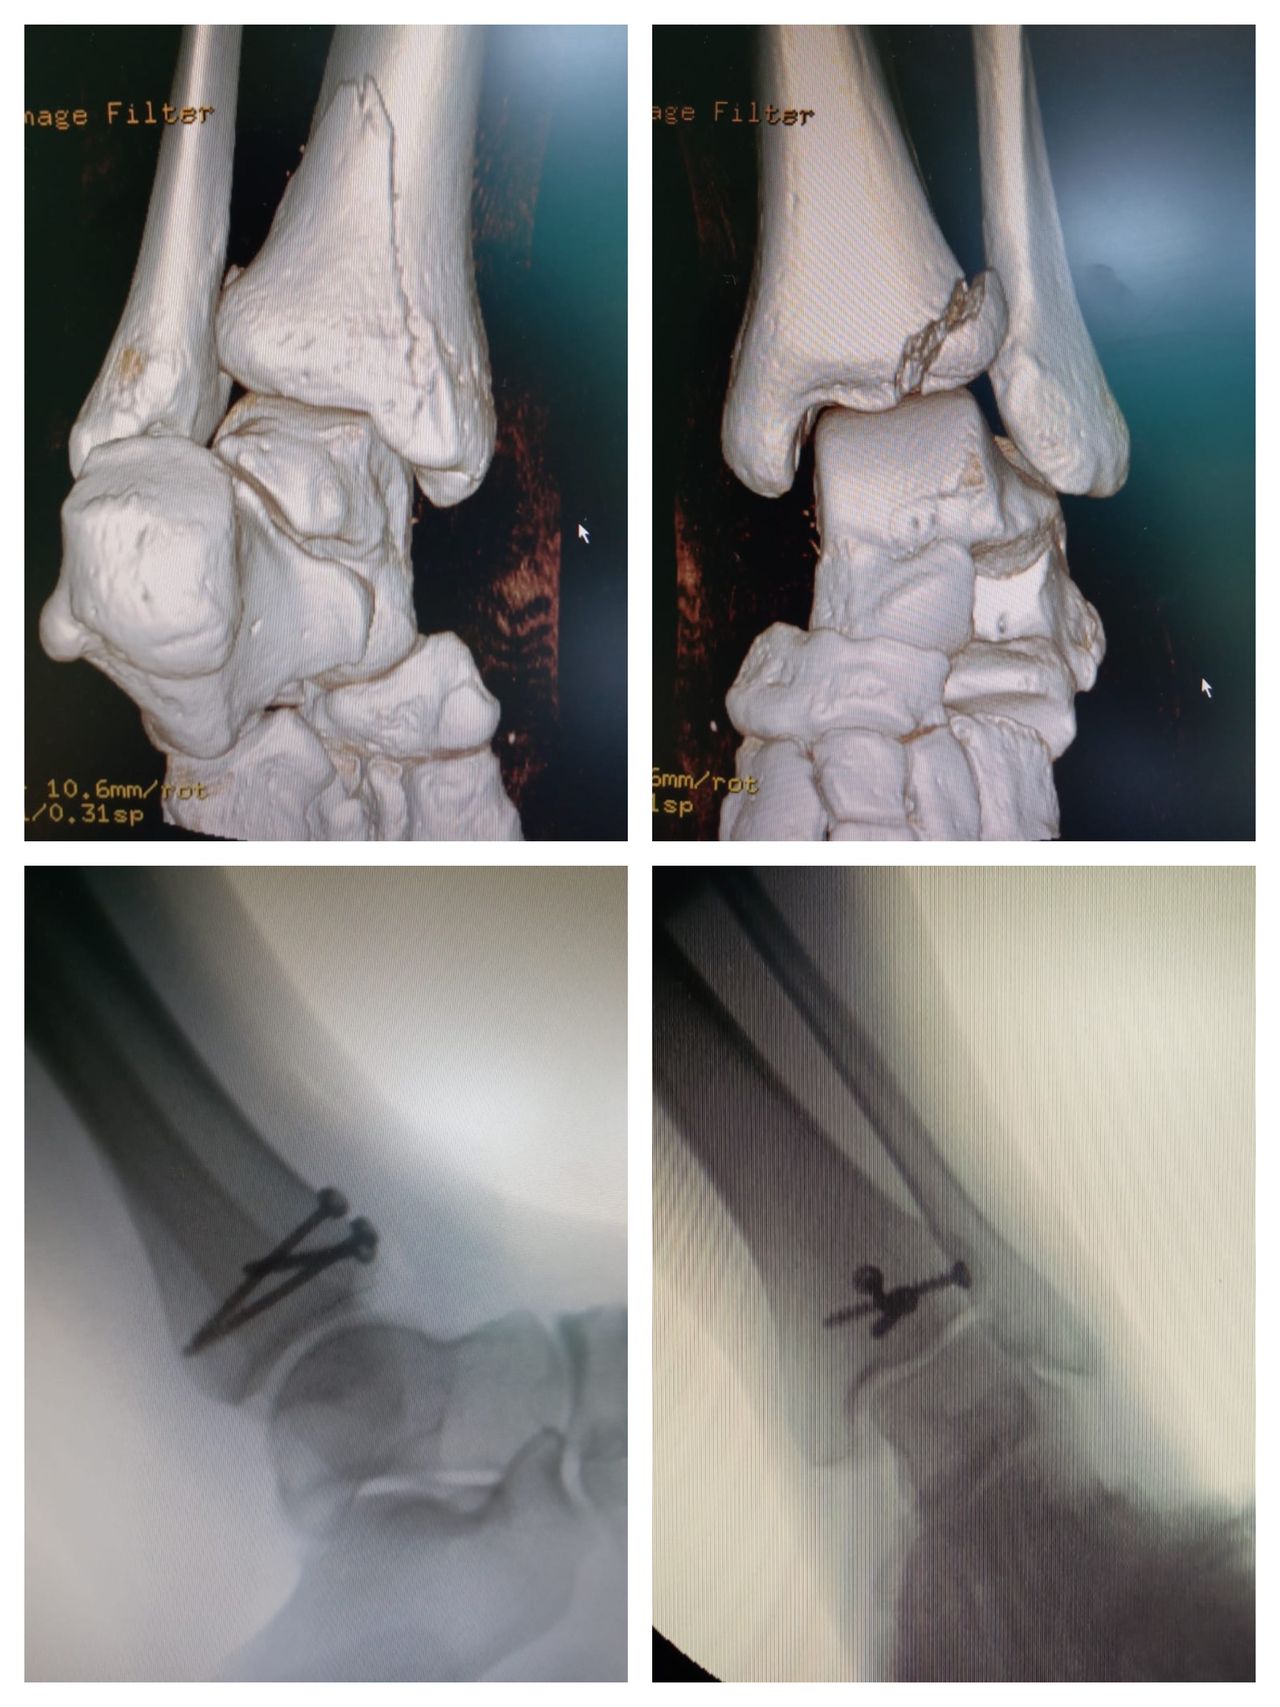

• Trattamento delle fratture dell’arto inferiore con tecniche moderne e sicure.

Foto e video